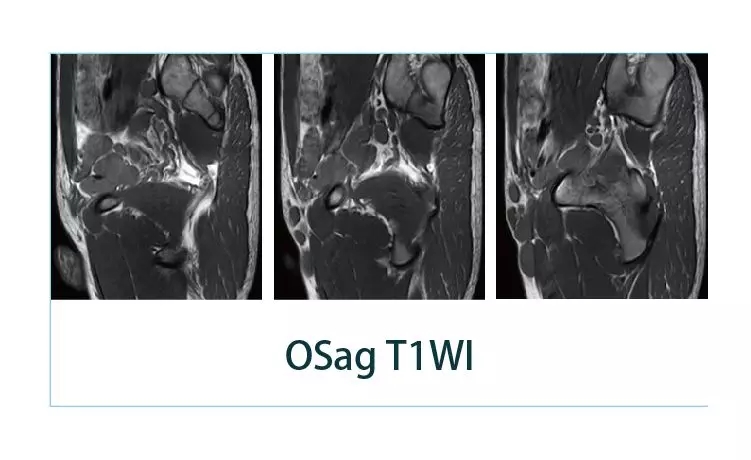

【朗润影像档案】20190405磁共振影像病例结果讨论